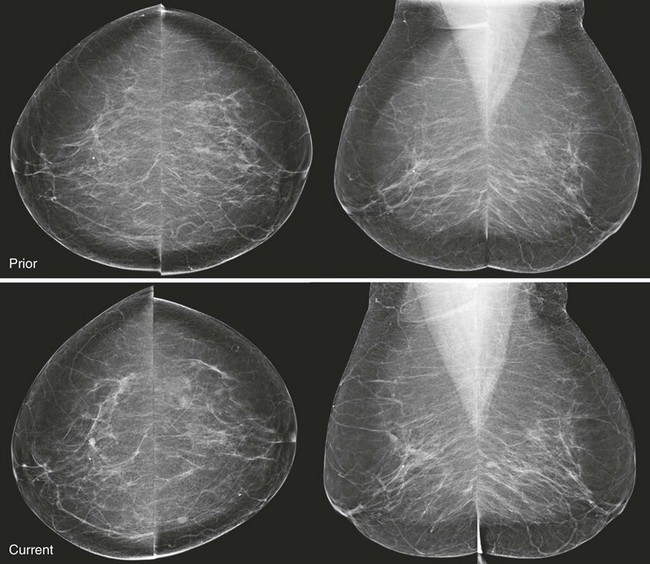

CASE 8-8. Screening mammogram on a 68-year-old woman with a comparison study from 2 years prior. What are the findings? What are your BI-RADS assessment and recommendation?

CASE 8-8. There are at least three new bilateral isodense masses with circumscribed margins (arrows). There were no masses on prior mammograms; therefore, diagnostic views and US were performed. CC spot compression views show circumscribed margins. US reveals bilateral oval solid masses. Core biopsy of masses in the 12 o’clock position of the right breast and the 10 o’clock position of the left breast both revealed previously unsuspected extranodal marginal zone B-cell lymphoma.